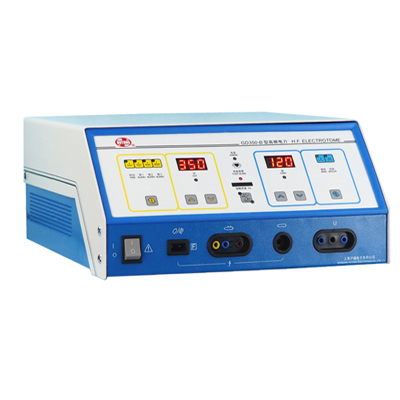

- 手術(shù)急救設(shè)備

- 無(wú)影燈 急救車(chē) 電動(dòng)手術(shù)臺(tái) 電動(dòng)吸引器 擔(dān)架 手術(shù)套車(chē) 吸痰器 麻醉機(jī) 電動(dòng)呼吸機(jī) 嬰兒培養(yǎng)箱 注射泵 電動(dòng)牽引床 輸液泵 電動(dòng)洗胃機(jī) 負(fù)壓調(diào)整器 腳踏吸引器 手術(shù)導(dǎo)航系統(tǒng) 化療泵 排痰機(jī) 心肺復(fù)蘇器